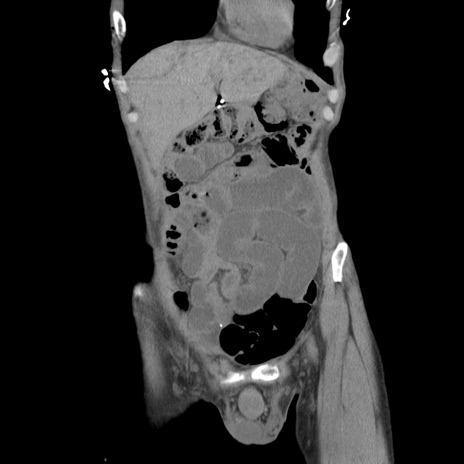

症例11(冠状断像)

【症例】 60歳代男性

【主訴】 下腹部痛

【現病歴】 本日夜中より下腹部痛の症状認め、受診。

【既往歴】 膀胱癌(膀胱全摘+尿管皮膚瘻術) 、胃癌術後

【身体所見】 BT 35.3℃、PR 58/min、BP 136/98mHg、腹部平坦、軟、腸蠕動音±、ストマ留置あり、左上腹部~正中部に圧痛あり、反跳痛なし。

【データ】WBC 5100、CRP0.01